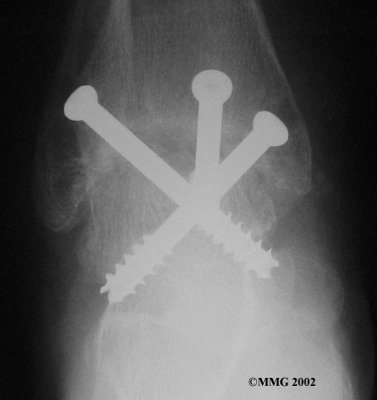

It is important when the surfaces are removed that the angles of the cut surfaces are correct. When the tibia is brought against the talus, the foot should be at a right angle to the lower leg. Once the cuts are made the bones must be held in place while they fuse. This can be done using large metal screws and metal plates if necessary. The screws are usually under the skin and are not removed unless they begin to rub and cause pain.

Inserting the screws

After ankle fusion, the physical therapists at FYZICAL Daphne can help you learn to walk smoothly and without a limp. Although time needed for recovery varies among patients, an ankle brace will typically replace your cast after eight to 12 weeks. Your surgeon will take X-rays frequently to see if the bones are fusing together. You will probably need to use crutches during the time you wear the cast. As the fusion grows stronger, you will begin to put more weight on your foot when walking.